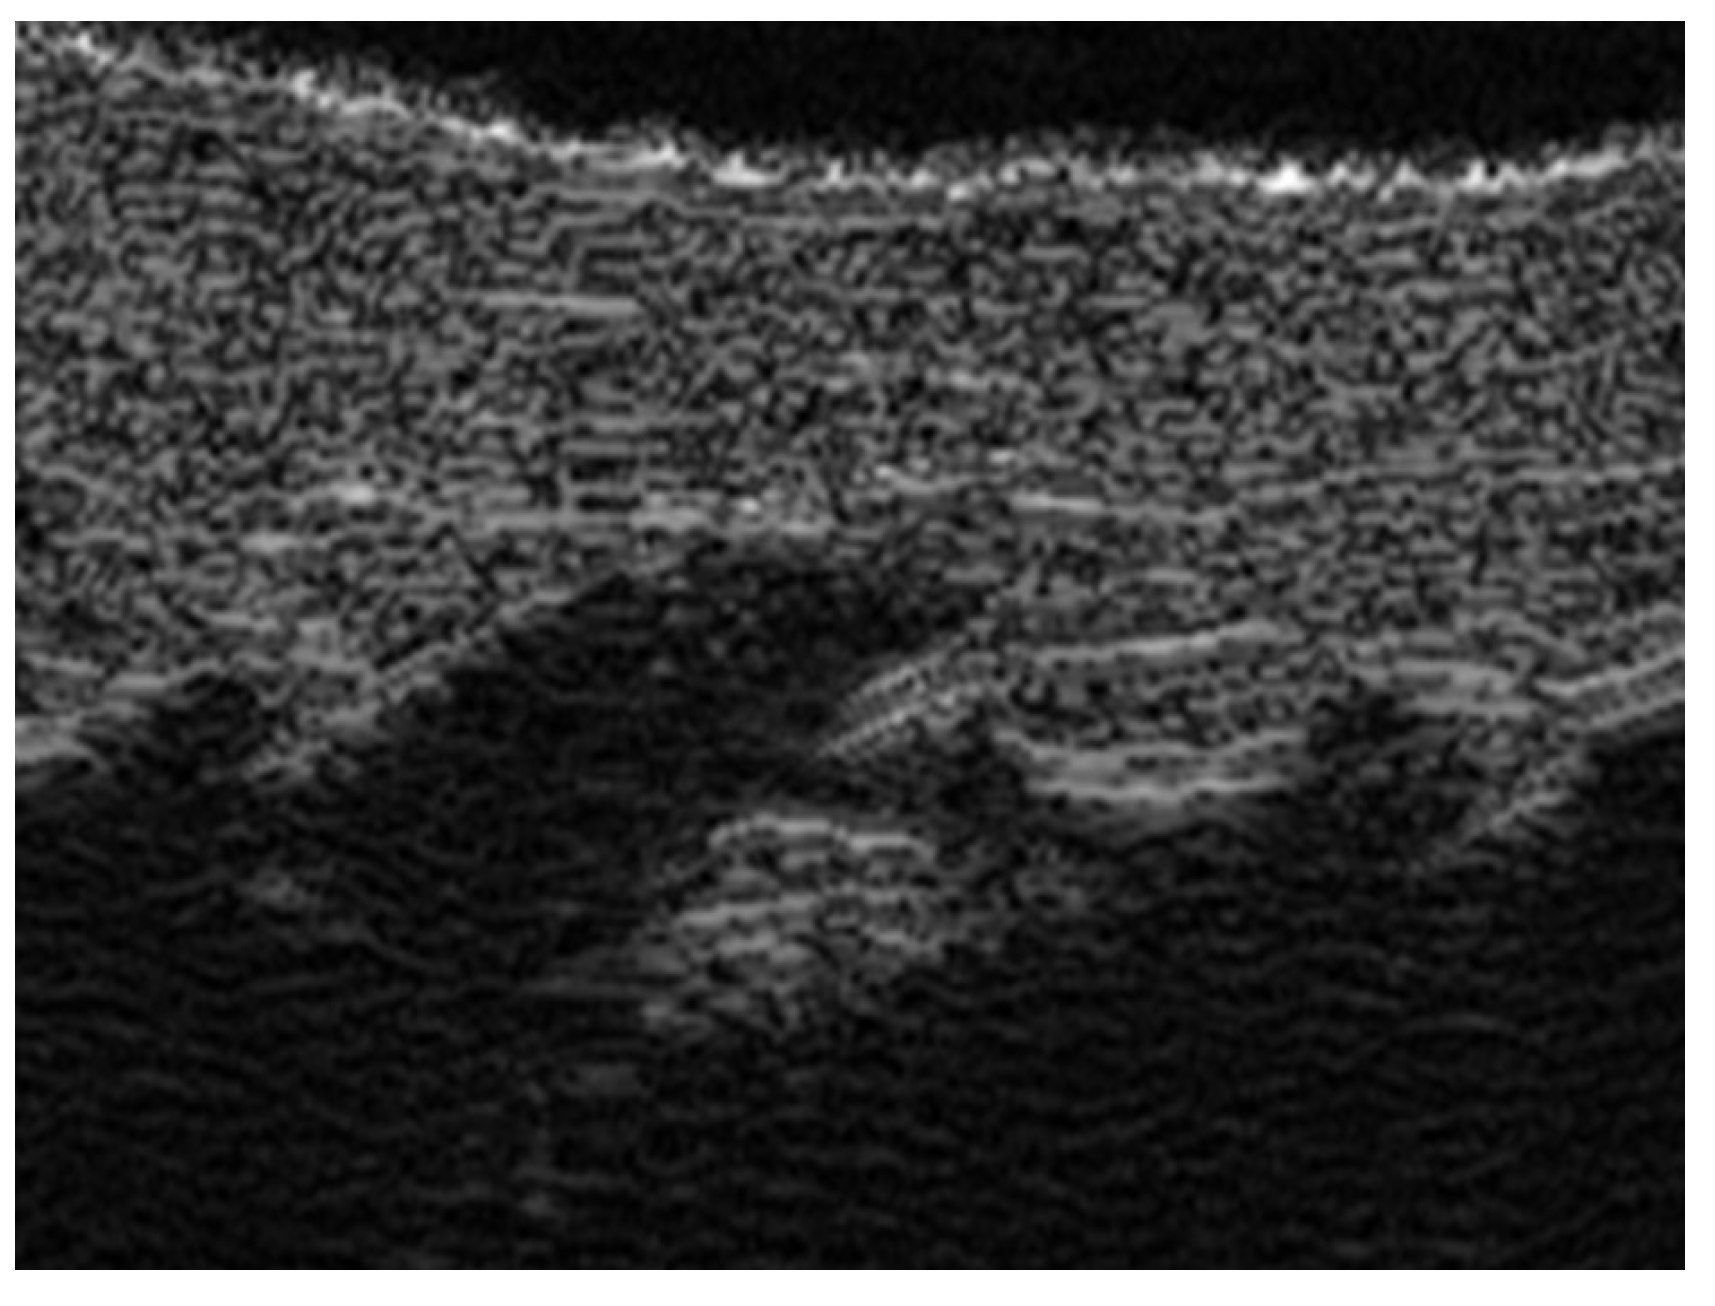

7. External-Agent-Associated Disorders

8. Neoplastic Diseases